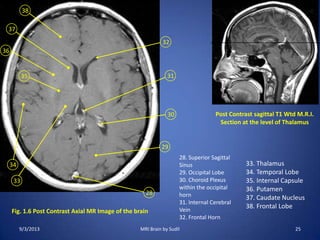

Fig. 1.6 Post Contrast Axial MR Image of the brain

28

29

30

31

32

38

33

34

36

35

37

Post Contrast sagittal T1 Wtd M.R.I.

Section at the level of Thalamus

28. Superior Sagittal

Sinus

29. Occipital Lobe

30. Choroid Plexus

within the occipital

horn

31. Internal Cerebral

Vein

32. Frontal Horn

33. Thalamus

34. Temporal Lobe

35. Internal Capsule

36. Putamen

37. Caudate Nucleus

38. Frontal Lobe

9/3/2013 25MRI Brain by Sudil